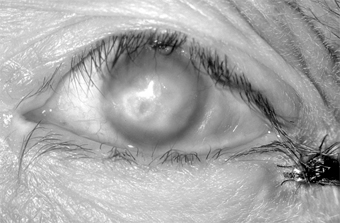

Complications & Sequelae

Conjunctival scarring is a frequent complication of trachoma and can destroy the ductules of the accessory lacrimal glands and obliterate the orifices of the lacrimal gland. These effects may drastically reduce the aqueous component of the precorneal tear film, and the film's mucous components may be reduced by loss of goblet cells. The scars may also cause distortion of the upper lid with inward deviation of individual lashes (trichiasis) or of the whole lid margin (entropion), so that the lashes constantly abrade the cornea. This often leads to corneal ulceration, bacterial corneal infections, and corneal scarring (Figure 5-2).

Figure 5-2

Figure 5-2: Advanced trachoma following corneal ulceration and scarring. Note the fly on the temporal aspect of the lower lid. The fly is a principal vector for trachoma.

Ptosis, nasolacrimal duct obstruction, and dacryocystitis are other common complications of trachoma.